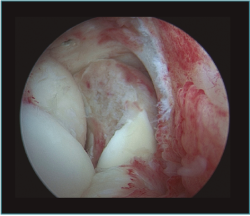

Figura 2. Visión artroscópica desde el portal anteromedial de un osteofito en la coronoides, disecado con un vaporizador de gancho, previamente a su resección con fresa motorizada.

Trabajaremos la parte ósea en primer lugar, resecando los osteofitos de la coronoides y de la fosa coronoidea, así como de la cabeza radial o de la articulación radiocubital si fuera necesario. Una vez hemos finalizado la parte ósea, procederemos realizar la capsulotomía anterior si está indicada.

La capsulotomía anterior la iniciaremos de medial a lateral, aproximadamente un centímetro proximal a la punta de la coronoides, utilizando un vaporizador "de gancho" (instrumento que nos parece muy útil para esta tarea, ya que nos permite controlar muy bien la profundidad de la resección de la cápsula para evitar lesionar estructuras neurovasculares próximas); también utilizamos la pinza Basket para resecar la cápsula, sobre todo en los casos en los que está muy engrosada y endurecida (Figura 7). Para disminuir el riesgo de lesión del nervio interóseo posterior (que queda cerca de la cápsula anterior al nivel de la cabeza del radio), dejamos intacta o parcialmente resecada la cápsula sobre la cabeza radial y completamos la capsulotomía con una extensión forzada del codo. Una vez hemos completado la capsulotomía anterior, veremos el tejido muscular del músculo braquial (Figura 8). En este momento no es recomendable resecar más hueso o tejidos blandos por diferentes motivos: al no tener la protección de la cápsula anterior, las estructuras vasculonerviosas están en mayor riesgo de lesionarse; además, en los casos de rigidez el músculo braquial puede ser más delgado, debido a atrofia muscular(14). Otro motivo es evitar el sangrado del músculo, para disminuir el riesgo de aparición de calcificaciones heterotópicas. En caso de ser necesario resecar hueso tras la capsulotomía, emplearíamos un separador a través de un portal anterolateral accesorio y el sinoviotomo o la fresa sin aspirador conectado (Vídeo, minutos 1:36-2:46).